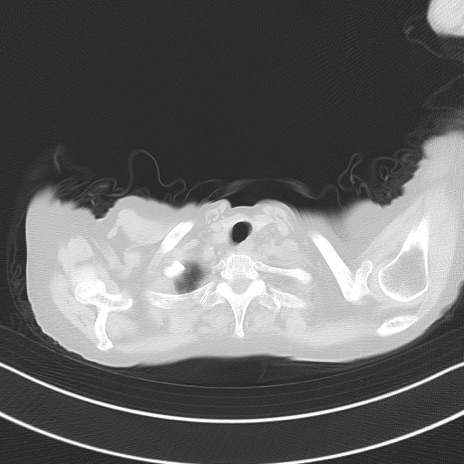

症例40(横断像)他院1日前

横断像

他院CT